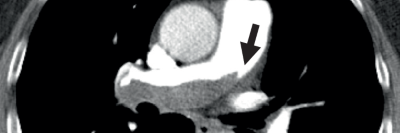

Tachykardie mit breiten QRS-Komplexen im EKG/© Trappe H-J et al. / all rights reserved Springer Medizin Verlag GmbH, Gastroskopie/© Lohmeyer JL et al. / all rights reserved Springer Medizin Verlag GmbH, Bewusstloser Mann/© chameleonseye / Getty Images / iStock (Symbolbild mit Fotomodellen), Kathetergestützte mechanische Thrombektomie /© Hecker M et al. / all rights reserved Springer Medizin Verlag GmbH, EKG-Kontrolle in einer Praxis/© Inside Creative House / Getty Images / iStock (Symbolbild mit Fotomodell), EKG auf Monitor/© sudok1 / Stock.adobe.com, Eine Frau zeiht Kompressionstrümpfe auf dem Teppich an/© dream@do / stock.adobe.com (Symbolbild mit Fotomodell), Person hält Tablette und Glas/© bilderstoeckchen / stock.adobe.com (Symbolbild mit Fotomodell), Frau hält Tabletten-Blister und Beipackzettel in der Hand/© Vladimir Vladimirov / Getty Images / iStock (Symbolbild mit Fotomodell), Medikamente und Medikationsplan/© Photographee.eu / stock.adobe.com, Zentrale Lungenembolie/© Springer Verlag Berlin Heidelberg 2015, Kaiserschnitt/© karegg / Stock.adobe.com (Symbolbild mit Fotomodellen), Älterer Mann schaut kritisch auf Tabletten/© Mediteraneo / stock.adobe.com (Symbolbild mit Fotomodell), Eine Person hält sich den Oberschenkel/© saran / Stock.adobe.com (Symbolbild mit Fotomodell), Chirurg führt Katheterablation durch/© Damian / stock.adobe.com (Symbolbild mit Fotomodellen), Älterer Mann mit Tabletten in der Hand/© vorDa / Getty Images / iStock (Symbolbild mit Fotomodell), EKG bei ventrikulärer Tachykardie/© Trappe H-J et al. / all rights reserved Springer Medizin Verlag GmbH, Heparin zur Antikoagulation/© Angel Arredondo / stock.adobe.com, Kolorektale Lebermetastase in Segment II, nahe der linken Lebervene (LHV)./© Sucher, E. et al. / all rights reserved Springer Medizin Verlag GmbH, Search Icon, FARAPULSE™ Joggende Frau im Park, Läuferin im Park/© PeopleImages / Shutterstock (Symbolbild mit Fotomodell); Boston Scientific Medizintechnik GmbH, Arzt erklärt Patient Operation am Laptop/© DC Studios / Adobestock (Symbolbild mit Fotomodellen), Arzt-Patienten-Gespräch, Junge Ärztin im Gespräch mit Patientin/© Parichat / Adobestock (Symbolbild mit Fotomodellen), FARAPULSE™ Joggendes Paar im Park/© JenkoAtaman / Adobe Stock (Symbolbild mit Fotomodellen); Boston Scientific Medizintechnik GmbH